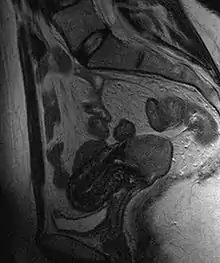

Cervical cancer seen on a T2-weighted sagittal MR image of the pelvis

This large squamous carcinoma (bottom of picture) has obliterated the cervix and invaded the lower uterine segment. The uterus also has a round leiomyoma up higher.

Often before the biopsy, the doctor asks for medical imaging to rule out other causes of woman's symptoms. Imaging modalities such as ultrasound, CT scan, and MRI have been used to look for alternating disease, spread of the tumor, and effect on adjacent structures. Typically, they appear as heterogeneous mass on the cervix.[53]